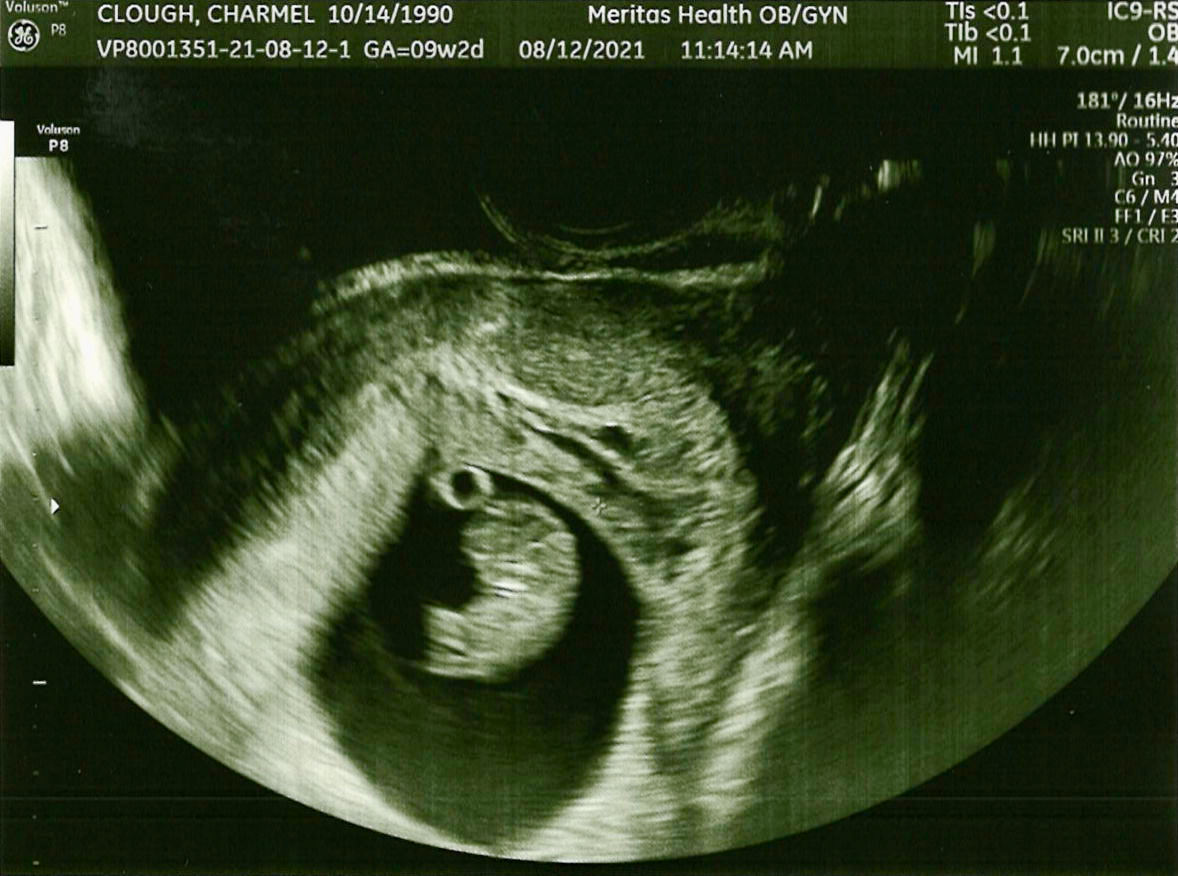

Baby Clough – 9.2 Weeks Gestation